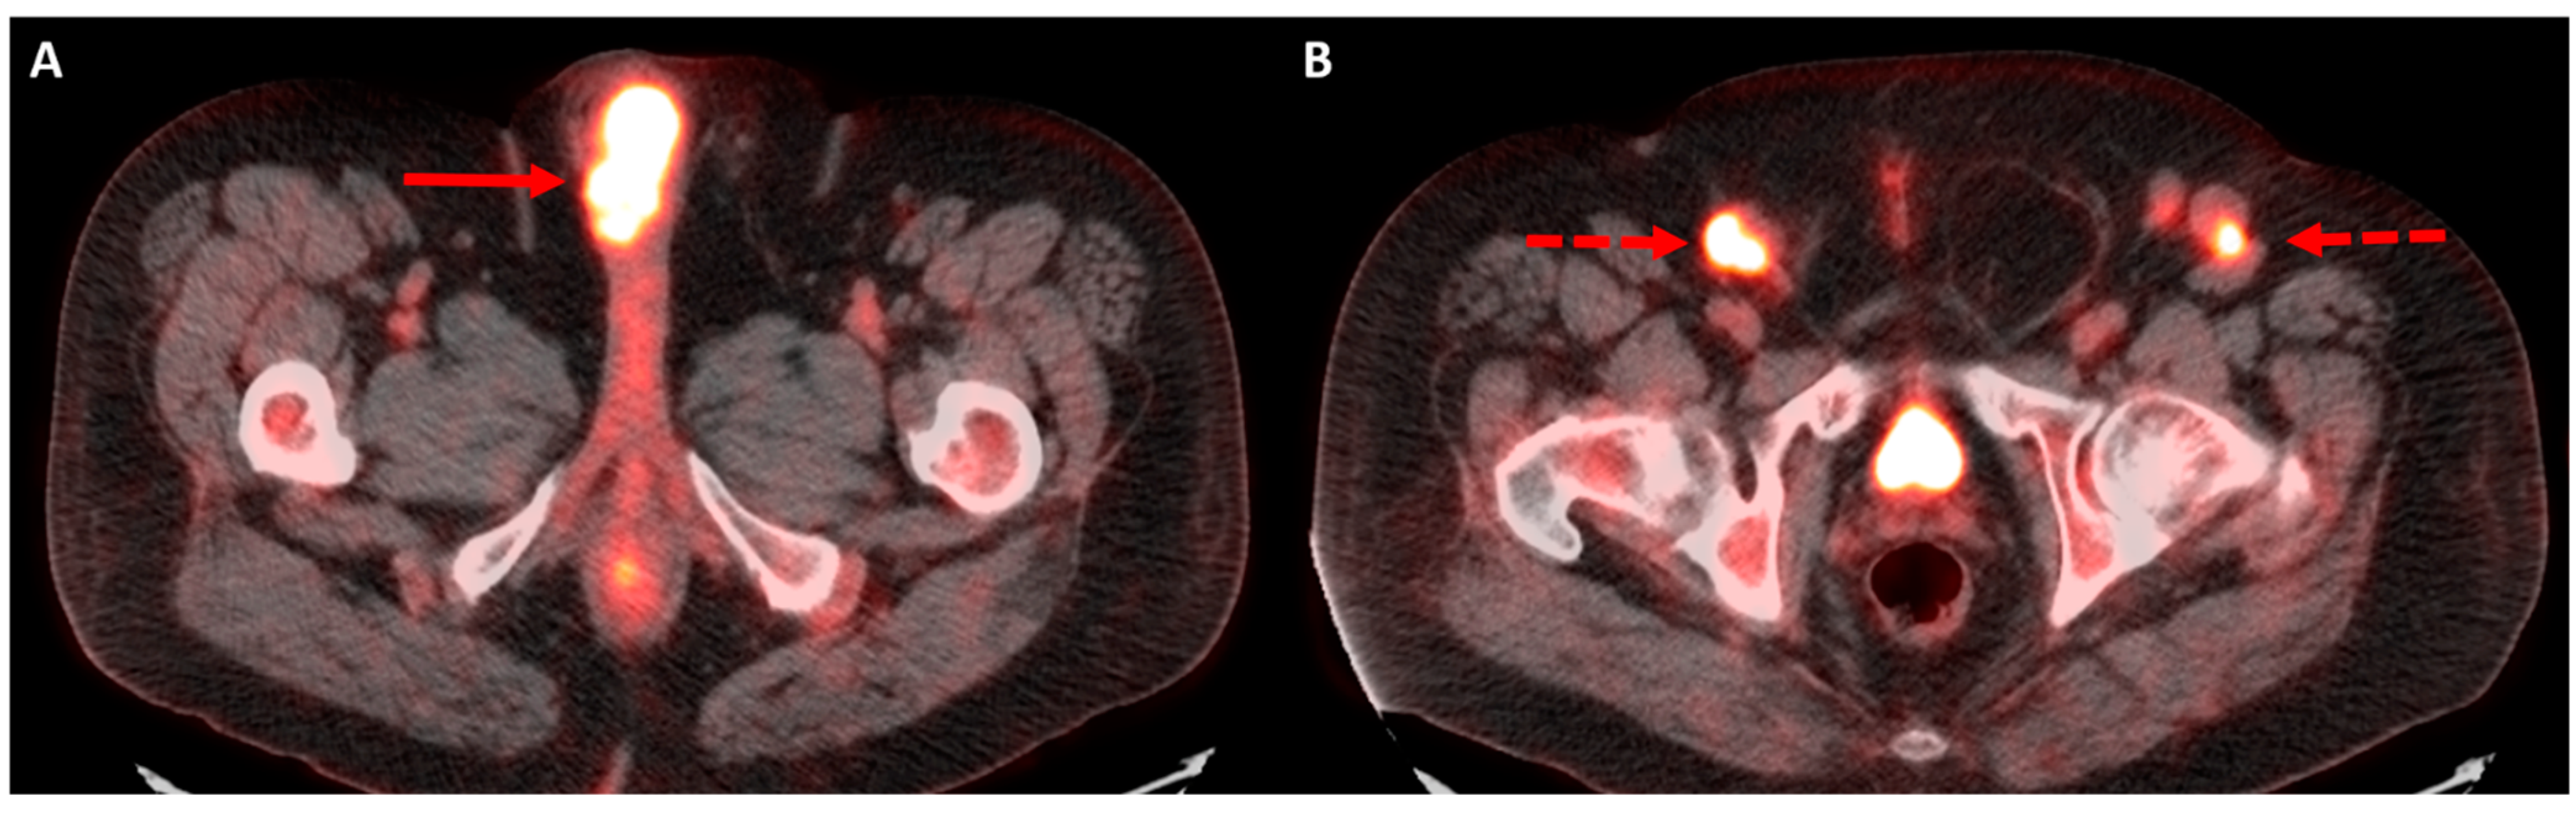

5. Positron Emission Tomography

5.1. Primary Staging

5.2. Restaging and Post-Treatment Surveillance